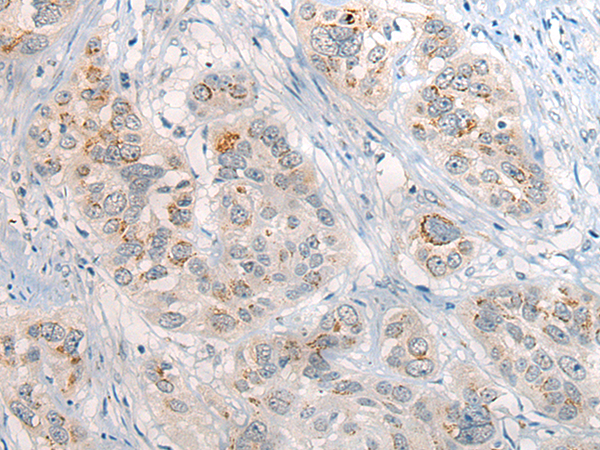

分类: 科研抗体货号: P13159别名: HNRPR; hnRNP-R应用: IHC反应种属: Human